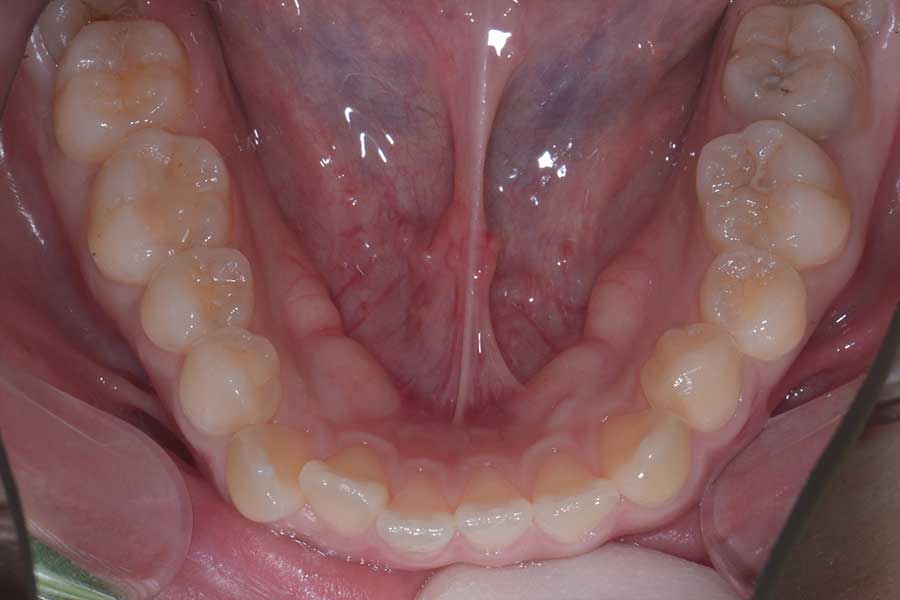

【20代女性】捻じれと段差と咬み合わせを治したい

• 治療前

主訴 捻じれと段差と咬み合わせを治したい

治療内容 上下顎ラビアル矯正(表側矯正)